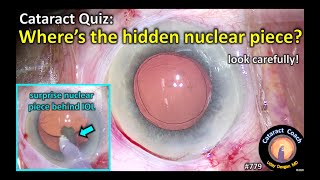

What Does a Cataract Look Like Inside Your Eye? (Visual Representation) Cataract Quiz: Where is the hidden nuclear piece in cataract surgery?

Cataract Quiz: Where is the hidden nuclear piece in cataract surgery?

What Does a Cataract Look Like Inside Your Eye? (Visual Representation) Cataract Quiz: Where is the hidden nuclear piece in cataract surgery?

Cataract Quiz: Where is the hidden nuclear piece in cataract surgery?